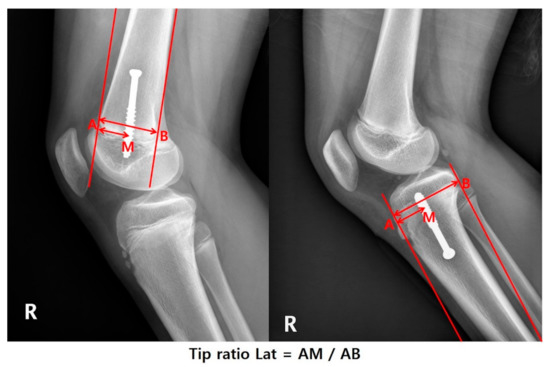

| Tip ratio AP | 0.64 ± 0.1 | 0.64 ± 0.09 | 0.63 ± 0.11 | 0.948 |

| Tip ratio Lat | 0.45 (0.39–0.5) | 0.41 (0.37–0.48) | 0.5 (0.47–0.54) | <0.001 |

| Tip ratio AP | −1.578 (−2.808 to −0.348) | −0.304 | 0.065 | |||

| Tip ratio Lat | −1.313 (−2.250 to −0.377) | −0.329 | 0.008 | |||

| ** Tip ratio Lat | Valgus | −0.203 (−1.740 to 1.333) | −0.040 | 0.797 | |||

| Varus | −1.543 (−2.507 to −0.58) | −0.595 | 0.006 | −1.218 (−2.107 to −0.33) | −0.470 | 0.016 | |

| ** Tip ratio Lat | Valgus | 3.059 (−4.684 to 10.802) | 0.119 | 0.443 | |||

| Varus | −6.750 (−11.838 to −1.662) | −0.523 | 0.018 | −4.238 (−8.828 to 0.352) | −0.328 | 0.090 | |